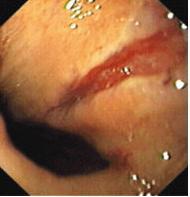

Síndrome de Mallory-Weiss o Desgarro de Mallory-Weiss. En medicina, el desgarro de Mallory-Weiss ó síndrome de Mallory-Weiss se refiere a laceraciones en la membrana mucosa del esófago, normalmente causados por hacer fuertes y prolongados esfuerzos para vomitar o toser. Puede aparecer con cierta frecuencia en el punto de unión entre el esófago y el estómago y puede acompañarse de sangrado.

El diagnóstico definitivo se realiza con una endoscopia y rara vez demostrable por radiología de rutina,aunque puede demostrarse con una angiografía después de una inyección de una sustancia de contraste